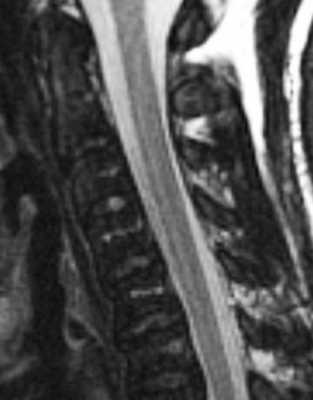

МРТ позвоночника. Т2-взвешенная сагиттальная МРТ шейного отдела позвоночника. Хронический миелолейкоз.